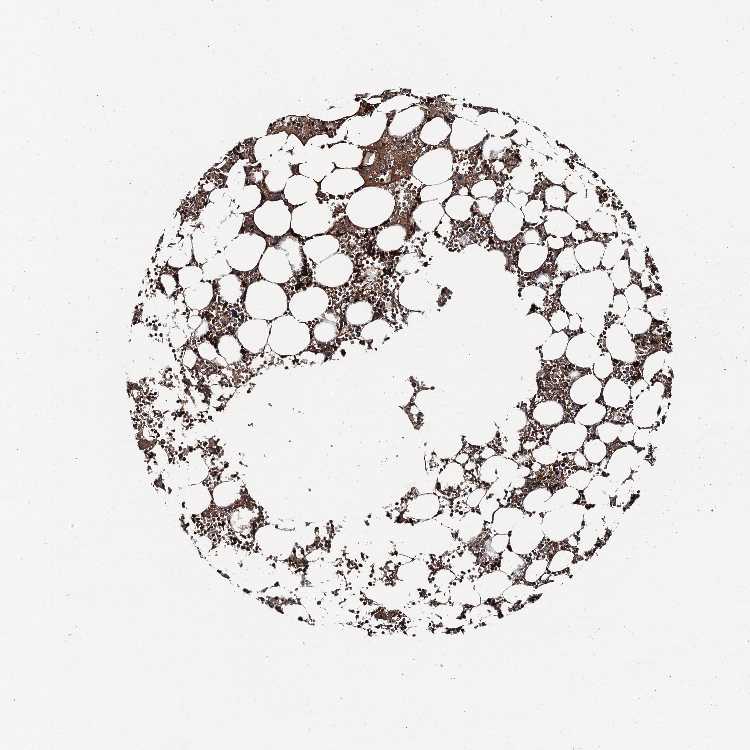

BONE MARROW - Antibody stainingi

Antibody staining in the annotated cell types in the current human tissue is reported as not detected, low, medium, or high, based on conventional immunohistochemistry profiling in selected tissues. This score is based on the combination of the staining intensity and fraction of stained cells.

Each image is clickable and will lead to virtual microscopy that enables deeper exploration of all samples and also displays staining intensity scores, fraction scores and subcellular localization as well as patient and tissue information for each sample.

Antibody HPA041775

Hematopoietic cells Medium